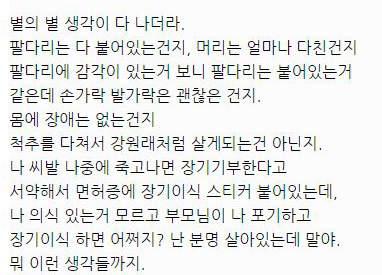

대단한 얘기는 아니지만 중환자실에 3주동안 무의식으로 있었던 썰 풀어볼게